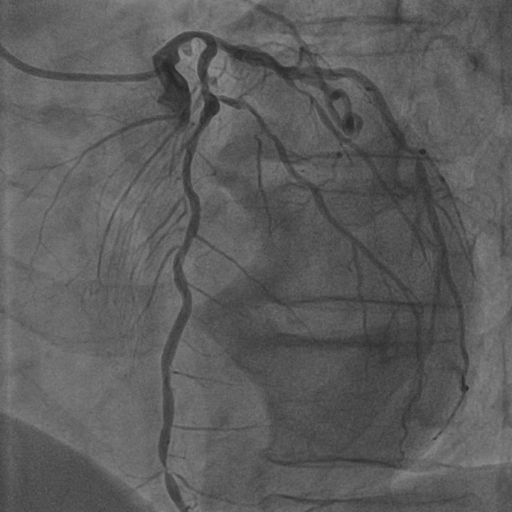

Coronary arteries (CAs) are essential for delivering oxygen-rich blood to the heart muscle [12]. To assess coronary artery circulation and diagnose disease, cardiologists traditionally use hemodynamic measures like fractional flow reserve (FFR) to determine stenosis severity [18]. Since pressure wire-based techniques are invasive and risky [61], X-ray coronary angiography (XCA) has emerged as a preferred method, using contrast agents to capture vessel structure while minimizing radiation exposure.

These challenges are exacerbated by XCA’s inherent limitations [64]: low signal-to-noise ratios, minimal radiation contrast [15], and interference from surrounding structures [41]. Existing automatic segmentation algorithms require extensive professional supervision and time-consuming annotation [22]. Single-image approaches discard critical temporal information and show poor adaptability across imaging systems. Additionally, involuntary organ motions and overlapping structures increase ghosting artifacts [35, 34], significantly limiting the practical application of current methods (Fig. 1).

4.1 XACV Dataset